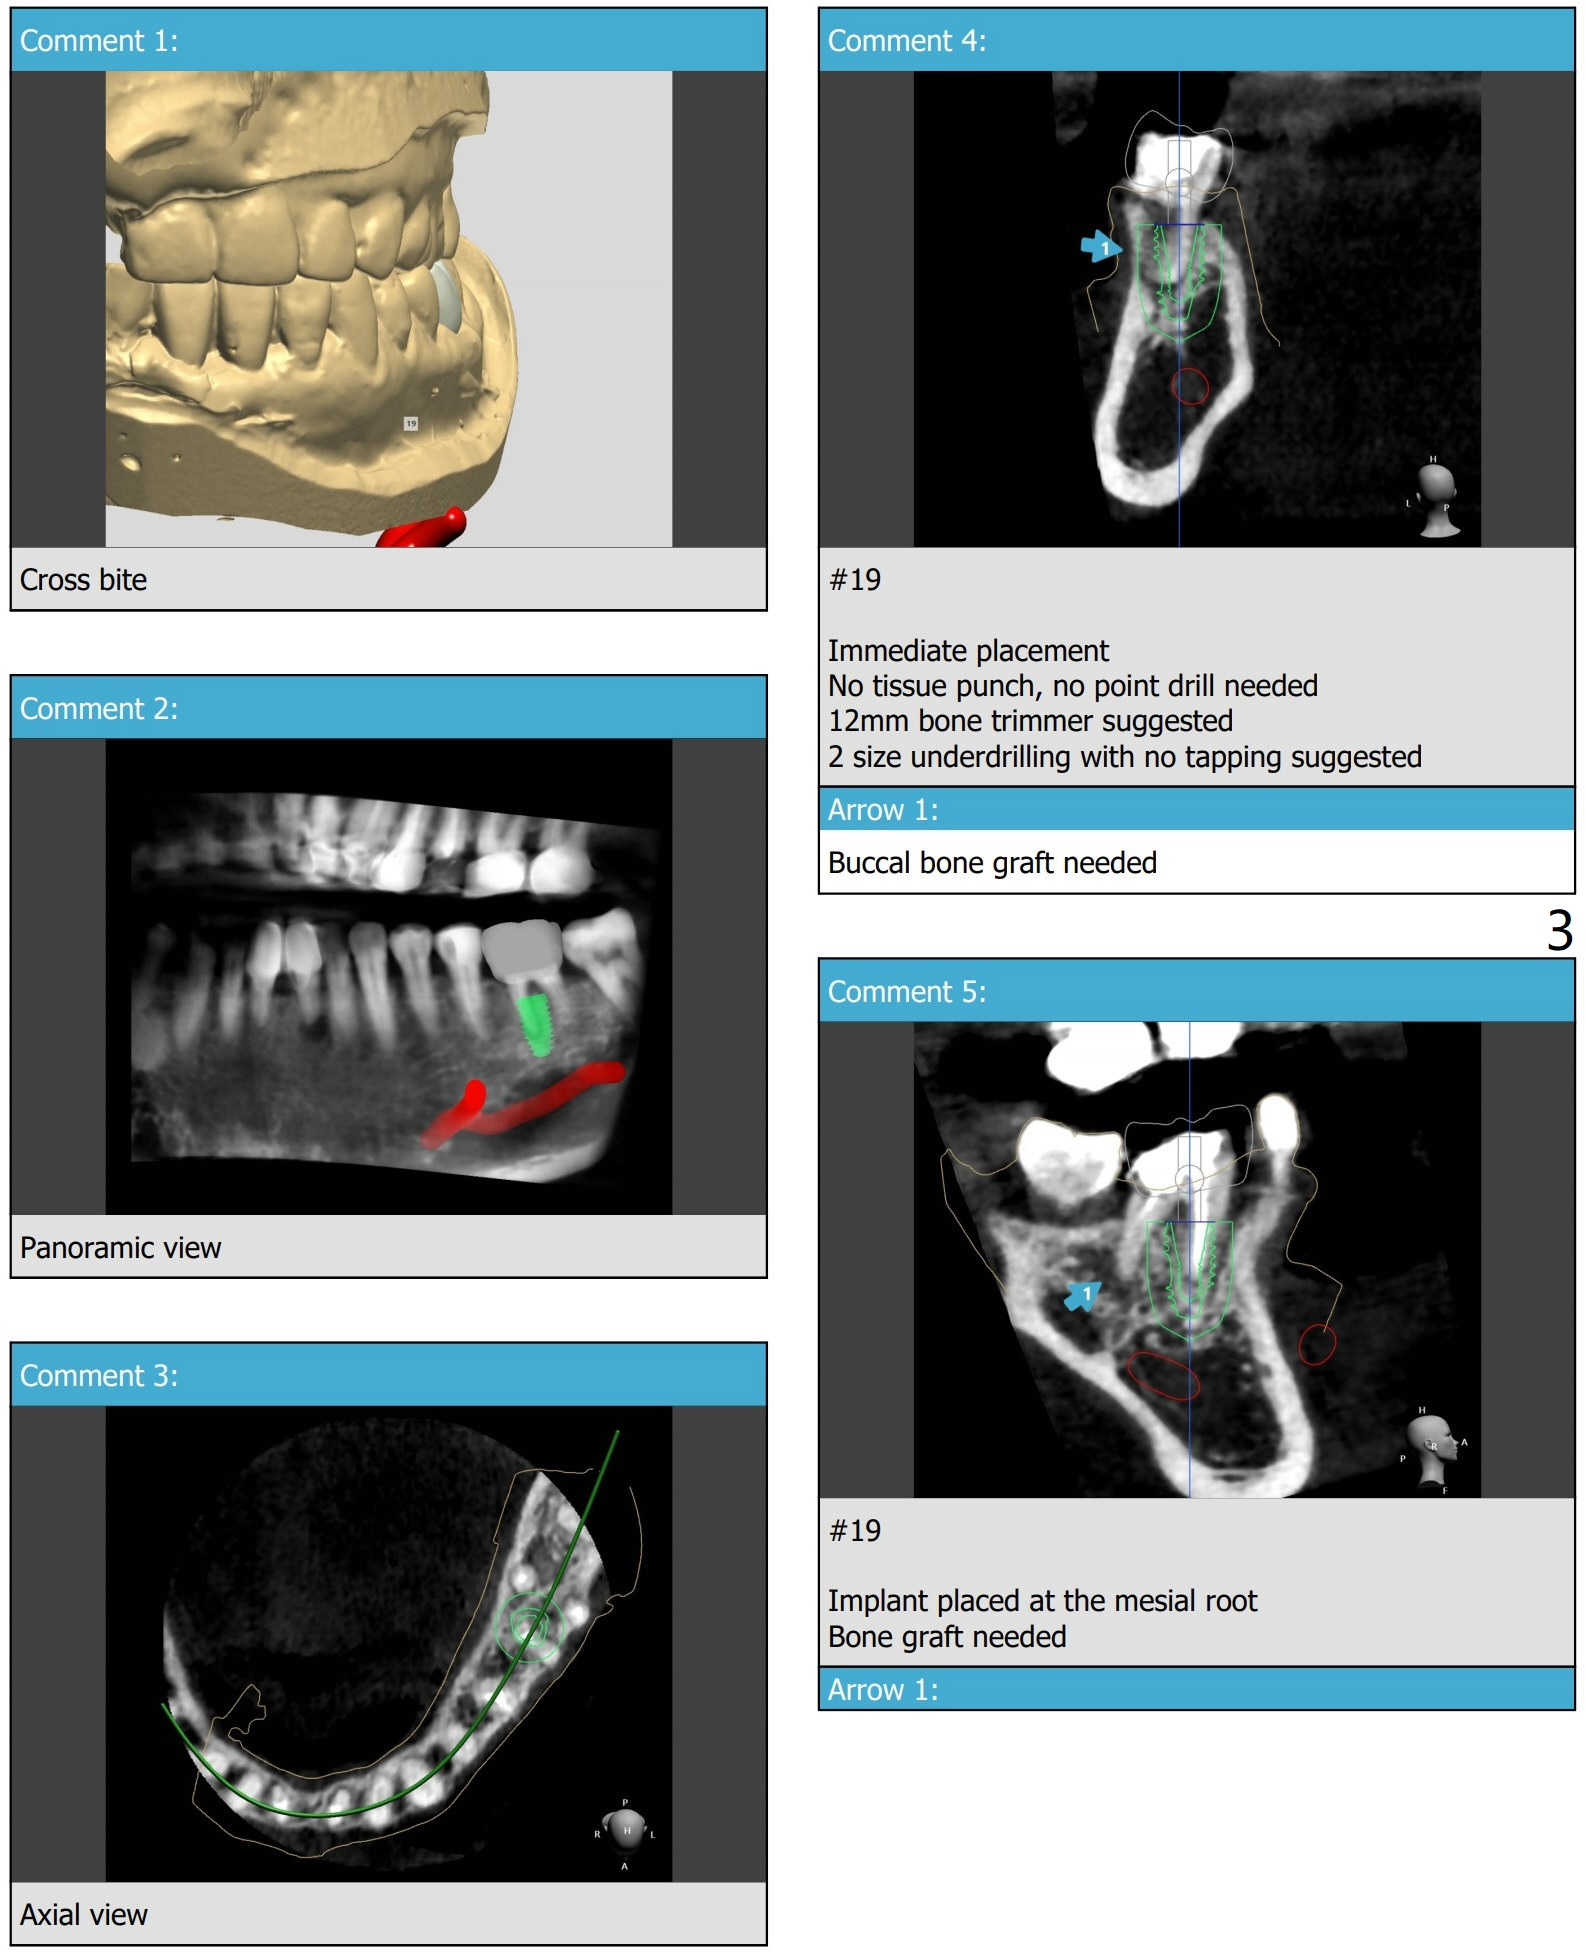

A 51-year-old woman has partially dislodged PFM crown at #19 with DL subgingival caries.